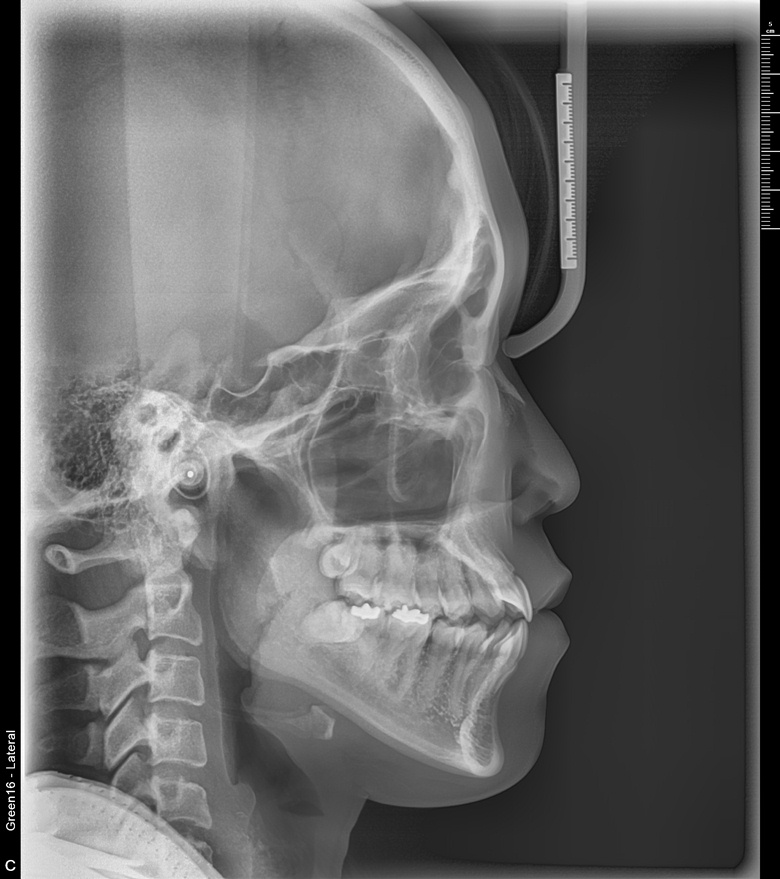

치료 전 사진입니다.